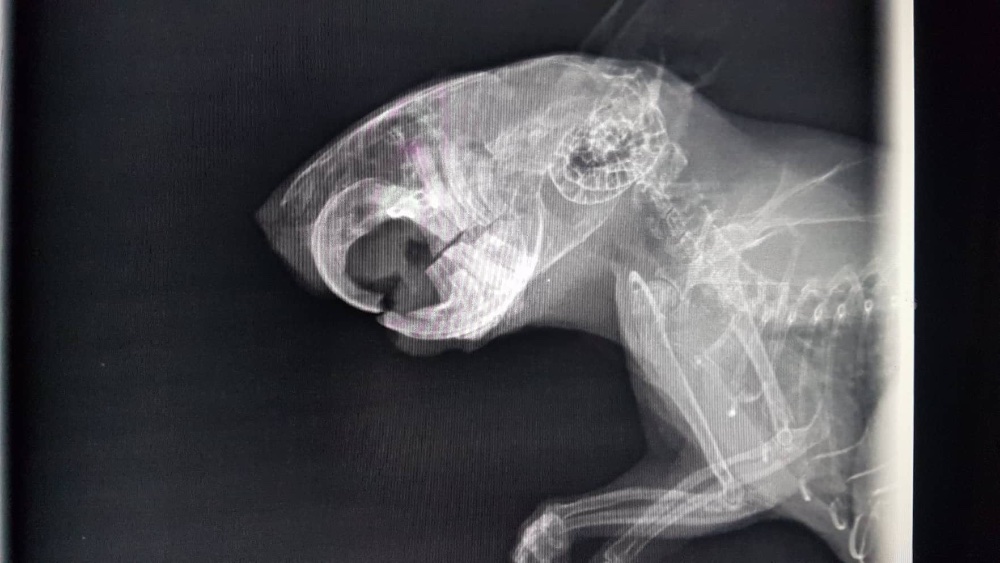

Also ab zum Tierarzt. Sie hat keine Veränderungen feststellen können - auch im Röntgenbild nicht. Er hat aber gefressen, nur eben langsam und eher die weichen Sachen. Nach ein paar Tagen wurden dann auch die unteren Schneidezähne schwarz

Und dann... tja, dann sind irgendwie alle Zähne nacheinander abgebrochen und sind in wunderschönem, gelblichen, gesunden Farbton wieder gekommen. Okay... ich verstehe es nicht, bin aber erstmal zufrieden. Trotzdem isst der blinde Zauberer nur mäßig festes Futter, schlingt aber den Brei. Also wieder mal zum Doc, wieder die Zähne gemacht, ein paar Spitzen geschliffen, aber sonst hat er gute Zähne. Auch das Röntgenbild scheint das zu bestätigen.

Und wenn ich mir sein letztes Röntgenbild so ansehe... irgendwie (jetzt wo man es weiß) sieht es schon da irgendwie anders aus, als hier

- merlin_roentgen.jpg (136.79 KiB) 2445 mal betrachtet